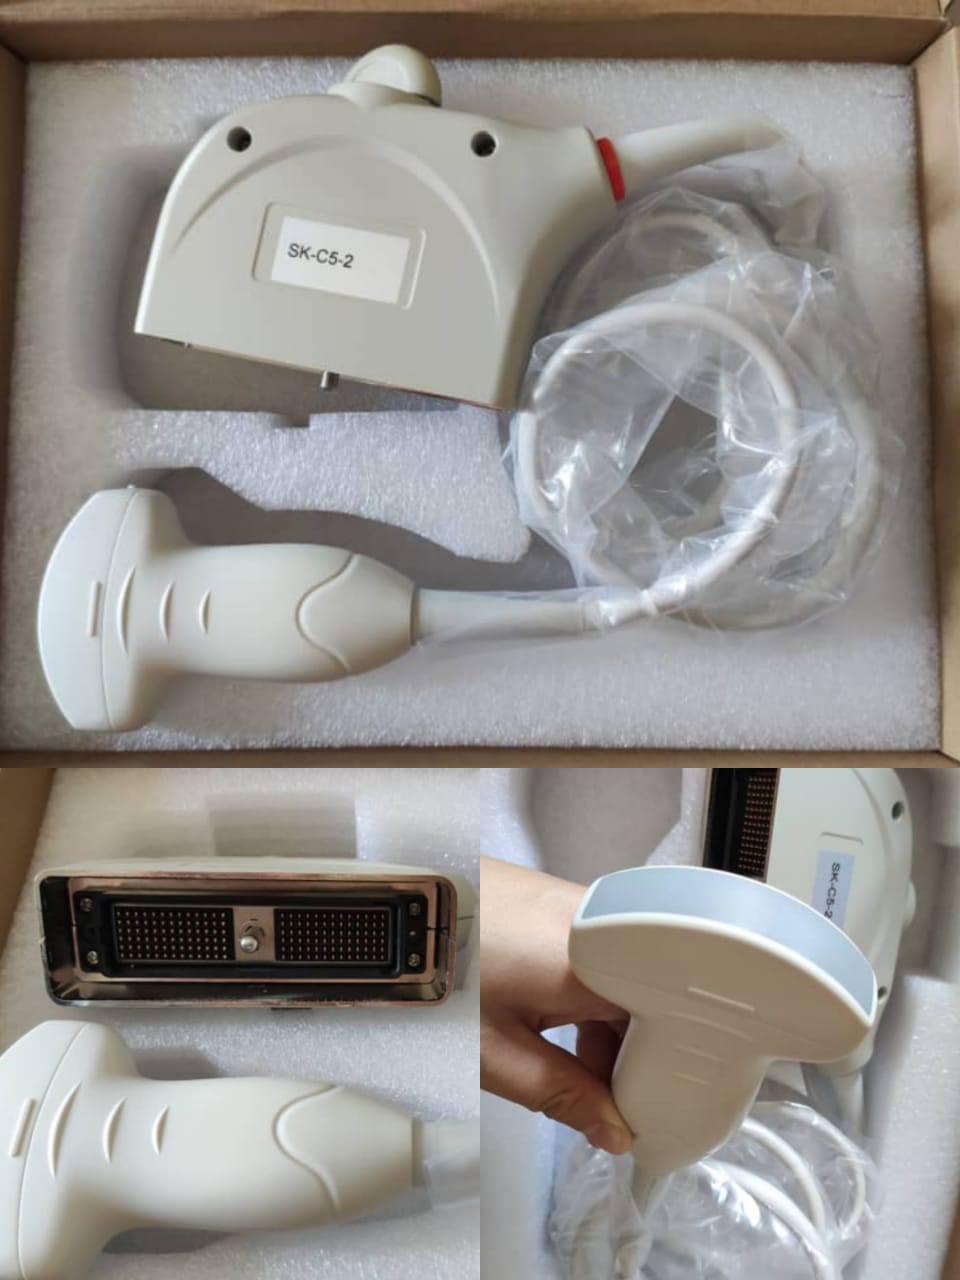

Mindray C5-2 New Convex Array Sensor Ultrasound Probe Ultrasonic Transducer

Mindray C5-2 New Convex Array Sensor Ultrasound Probe Ultrasonic Transducer